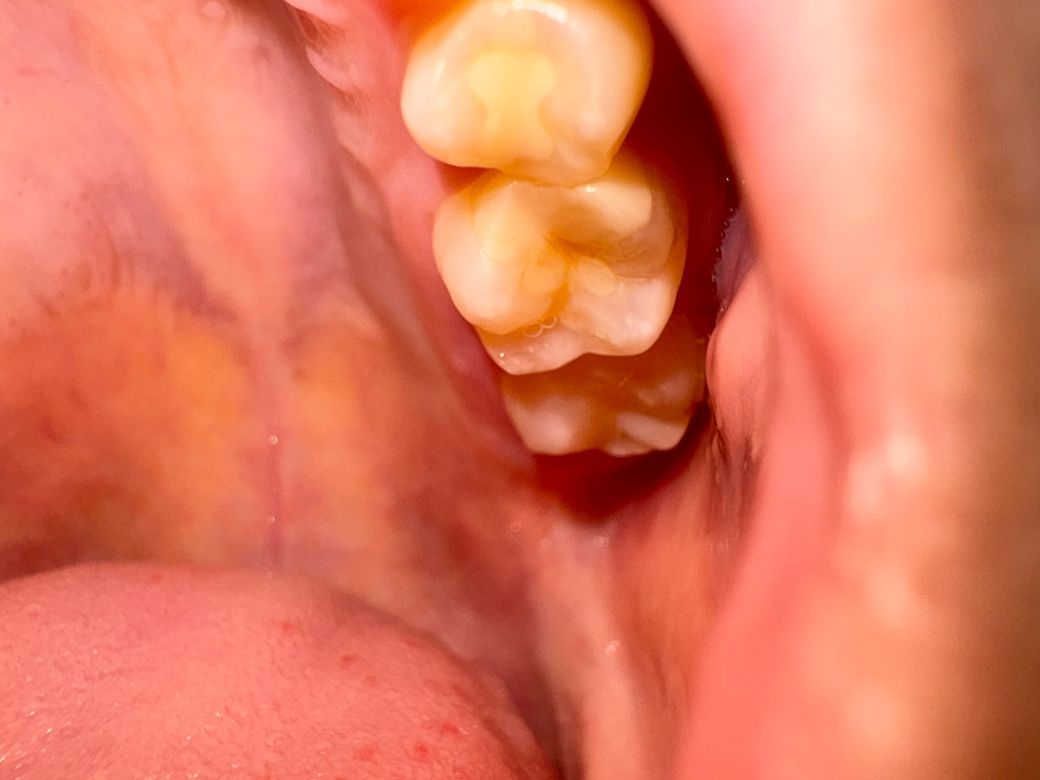

파절아니면 금산거 같아서요 통증은 꽉물어도 없고 신경치료 안받았어요 이제껏 아프진 않았는데 양치하고 혀로 확인하다가 구멍이 느껴져서 .. 최대한 사진 찍어봤습니다 충치나 혹여나 가격이 얼마나 나올까요..? 예전에 지르코니아로 했어서..

현재 사진에서는 치아 자체가 부러지거나 하지는 않은것 같습니다. 부러지더라도 경미한 것으로 보여지며 예전에 치료했던 부위가 떨어진 것 같습니다. 이러한 경우에는 다시 해당 부위를 수복할 수 있는 방법이 있습니다. 음식물이 쌓이고 더 파절되기 전에 가까운 치과를 방문하여 치료를 권해드립니다.

부분적으로 깨진 것이 맞아보입니다. 충치는 아닌 것으로 보이며 비용도 치과마다 차이가 있습니다.

일단은 치과에 가셔서 검진을 받아보시고 다시 인레이로 한다면 재료에 따라서25-35까지 할꺼고 크라운은 35-60만원까지 가격이 형성되어 있습니다.

인레일 했던게 떨어져 나간 것 같습니다. 치아 상태 보고 별다른 이상 없다면 다시 동일한 인레이로 본뜨고 떼우면 될 것 같습니다.